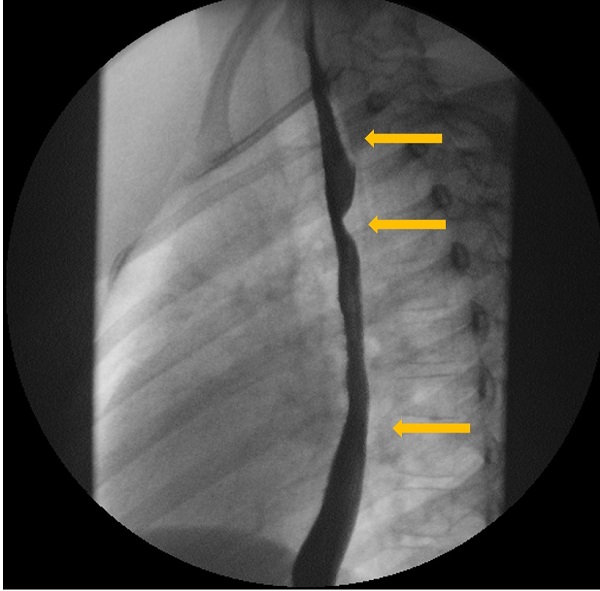

La exploración física es normal, con adecuado desarrollo ponderoestatural. Se realiza un estudio esófago-gastroduodenal con contraste baritado, en el que se pone de manifiesto una impronta sobre la pared posterior de la porción torácica del esófago, en relación con diagnóstico ya conocido de arteria subclavia derecha aberrante (Figs. 1, 2 y 3).

| Figura 2. Estudio esófago-gastroduodenal con contraste baritado. Proyección anteroposterior. Se observa la impronta oblicua de la arteria subclavia derecha aberrante (ARSA) en el tercio medio esofágico y la ralentización del flujo del contraste baritado a su través |

|---|

![]() |